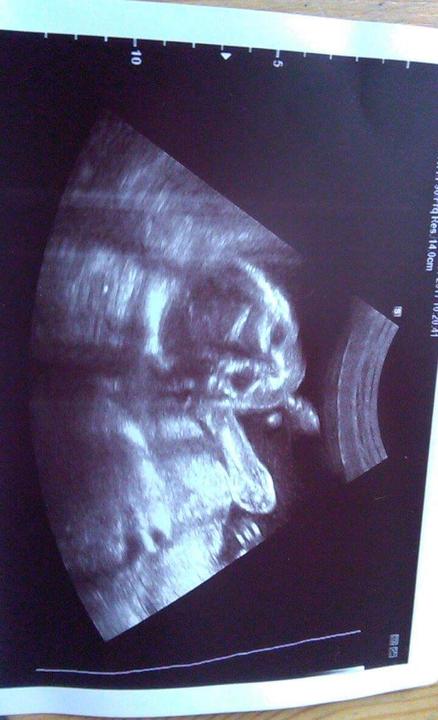

Den první (12.1.2017):

Ráno jsem vypravila partnera do práce, vyvenčila hafana, uvařila si čaj a jen tak vegetila. To jsem ještě nevěděla, že je to poslední dopoledne doma bez Tebe :-*

Dala jsem péct králíka a šla poklidit psa. Po obědě jsem si dala kávu a rozhodla jsem se, že bych mohla začít skládat druhou čtvrtinu z 6000 puzzle. Postavila jsem jen rámeček a jeden pruh, který rozděluje vodní hladinu a domečky.

16:30 - Najednou jsem měla pocit, že jsem si 2x cvrkla. Šla jsem na záchod a tam se to spustilo. Pořád jsem nevěděla, jestli čůrám, nebo to teče samo. Verdikt jsem vyslovila, když jsem cítila, že to přestalo téct, ale když jsem se postavila z WC, znovu se to spustilo. Bylo to jasné - je to voda. Když jsem vyšla ze záchodu, partner na mě volal z garáže: "Lásko, už jsem doma z práce." Uvařila jsem mu kávu a šla za ním.

Řekla jsem mu, že se asi něco začíná dít, protože mi teče voda a že si má vypít v klidu kávu, okoupat se a já že se dobalím a pomalu pojedeme do porodnice.

ON: "To jako vážně??"